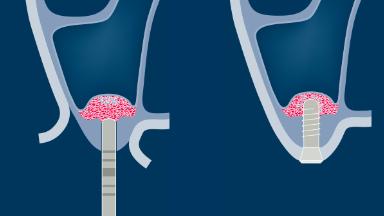

Following tooth loss, alveolar resorption and ongoing pneumatization of the maxillary sinus may lead to vertical bone deficits in the posterior maxilla.

This deficit reduces the distance between the maxillary sinus floor and the alveolar process, so that reconstructing the vertical bone height may be a prerequisite for placement of dental implants of the correct dimensions and in the ideal three-dimensional position while respecting anatomical structures.

Sinus floor elevation is a predictable procedure for vertical bone augmentation in the posterior maxilla that compensates for inadequate bone height. Grafting material is placed into the sinus to increase available bone height and to facilitate the placement of implants of the desired dimensions and in the correct prosthetically driven positions.

Sinus floor elevation can be performed by lateral window or transcrestal approaches.